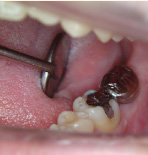

エンドシステム

歯の根の治療は基本的な治療ですがとても複雑。

専用機器を使ったシステマチックな治療で効率良い処置を行っています。

- エンドシステム

- エンドシステム治療